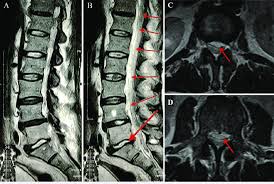

Retrolisthesis lumbar involves backward vertebral slippage in the lower spine. Vertebrae misalign, compressing nearby structures. This condition differs from anterolisthesis, where slippage occurs forward. It primarily affects the lumbar region due to weight-bearing stress. Degeneration weakens discs and ligaments over time. Trauma accelerates the onset in younger individuals. Genetic factors influence susceptibility in families. Instability leads to joint dysfunction quickly. Patients notice posture changes subtly. Medical imaging confirms the diagnosis accurately. Grades measure slippage severity from 1 to 4. Mild cases show less than 25% displacement. Severe instances exceed 75% shift.

Physicians perform physical exams to assess retrolisthesis lumbar initially. They check range of motion and tenderness. X-rays reveal vertebral alignment clearly. MRI scans show soft tissue details precisely. CT scans provide bone structure views. Nerve conduction tests evaluate compression effects. Blood tests rule out infections. Grading systems classify slippage degrees.

Palpation identifies tender spots accurately. Flexion tests provoke symptoms reliably. Extension maneuvers highlight instability. Lateral X-rays measure displacement in millimeters. Sagittal views confirm backward shift. Bone density scans detect osteoporosis links. Electromyography assesses muscle function. Differential diagnosis excludes similar conditions.

Diagrams aid in explaining diagnostic imaging.